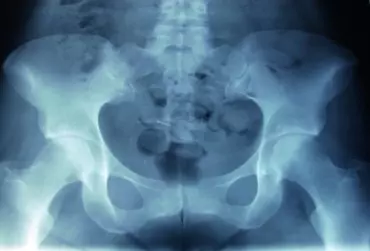

Diagnostyka stawu krzyżowo-biodrowego dla potrzeb fizjoterapii

Dolegliwości bólowe okolicy lędźwiowo-krzyżowej są objawem niespecyficznym i właściwym dla wielu jednostek chorobowych [1]. Określenie jednoznacznej etiologii jest trudne z powodu występowania zespołu nakładania bądź istnienia ścisłych zależności patogenicznych pomiędzy jednostkami chorobowymi wchodzącymi w skład wymienionych grup [2]. Dlatego też w procesie stawiania prawidłowej diagnozy wysuwa się  przeprowadzenie rzetelnego badania przedmiotowego i podmiotowego oraz diagnostyki różnicowej. Celem niniejszego artykułu jest przedstawienie diagnostyki stawu krzyżowo-biodrowego dla potrzeb fizjoterapii.